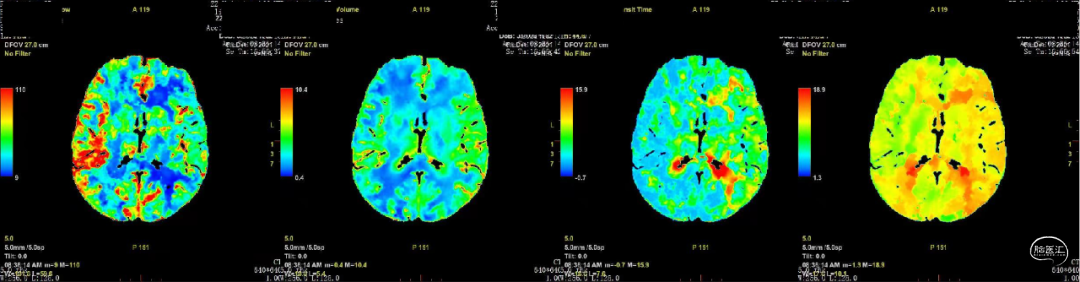

颅脑ASL(入院后):右侧大脑中动脉供血区低灌注。

CTP: